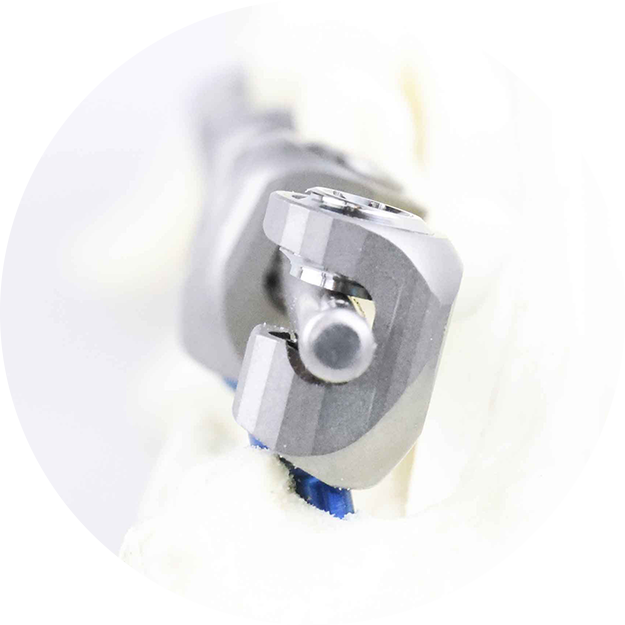

Side-Loading Rod Placement for Stability

Positioning the rod closer to the bone shortens the lever arm and reduces stress on screw threads and surrounding bone. This biomechanical advantage translates into lower risk of screw loosening and improved force transmission, ensuring stable vertebral under load.

Asymmetric Screw Head for Anatomical Integration

The asymmetric tulip head adapts to the natural contour of the vertebrae, creating a secure bone-comforting fit. Unlike symmetrical designs, this geometry reduces micro-motion at the bone-implant interface, which in turn minimizes soft tissue irritation.

Variable Polyaxial Angulation for Surgical Flexibility

The screw heads allow controlled polyaxial angulation, giving surgeons the ability to fine-tune screw alighnment and rod placement even in anatomically challenging or distorted spinal regions, making implantation safer and more precise.

Compact, Tissue-Sparing Profile

The compact design of the screw head and rod construct facilitates implantation in tight anatomical corridors, reduces implant prominence and protects surrounding musculature and vascular structures from irritation or damage.